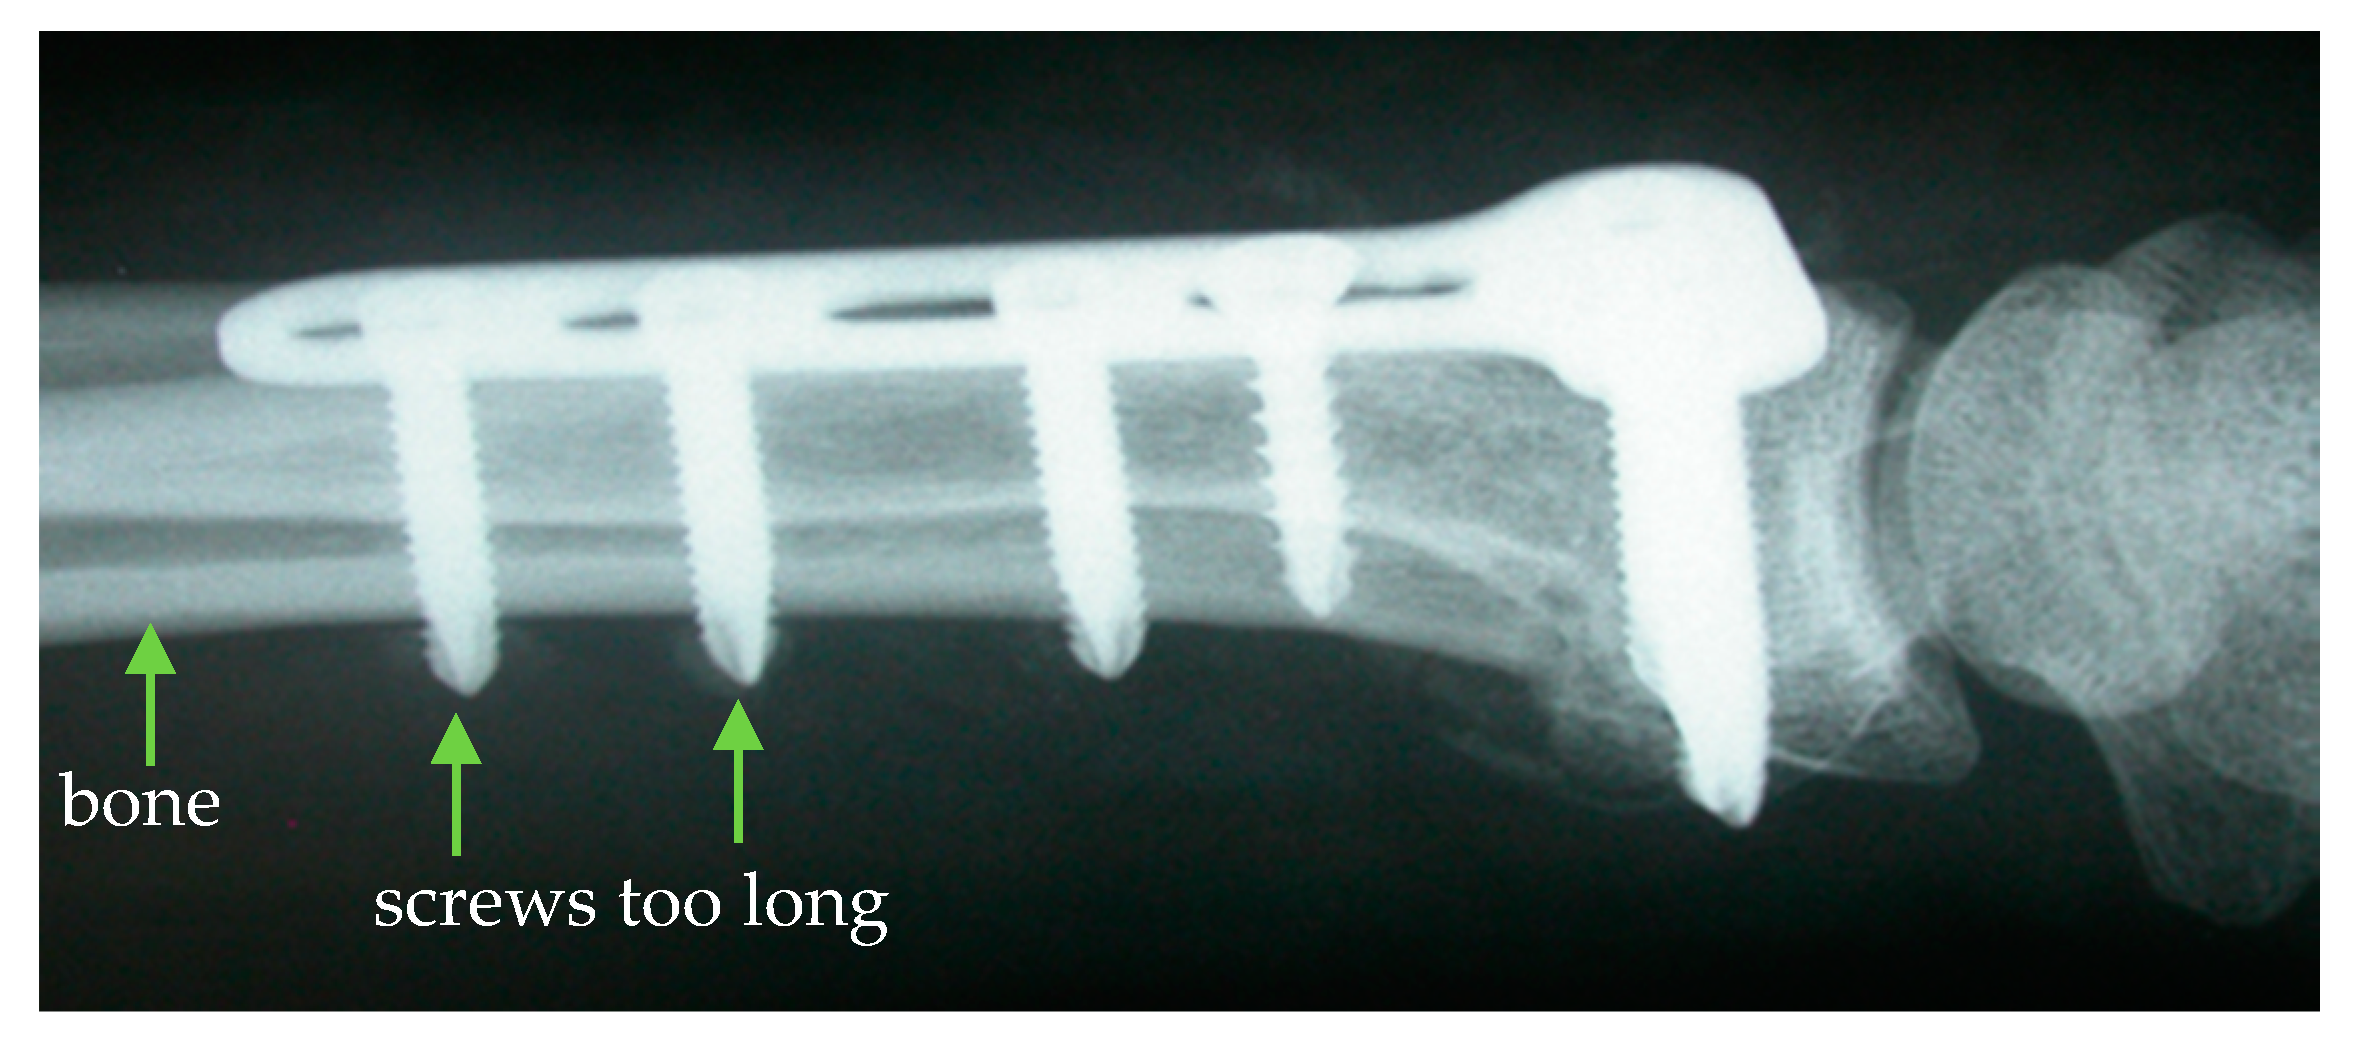

However, the determination of the drill channel length is subject to a high degree of uncertainty, which regularly leads to an incorrect determination of the required screw length. The most common treatment error resulting from this is a screw protrusion in which the screw ends protrude from the bone and can injure adjacent tissue (Figure 1) [3].

Figure 1. Screw protrusion due to an incorrect determination of the drill channel length [4].